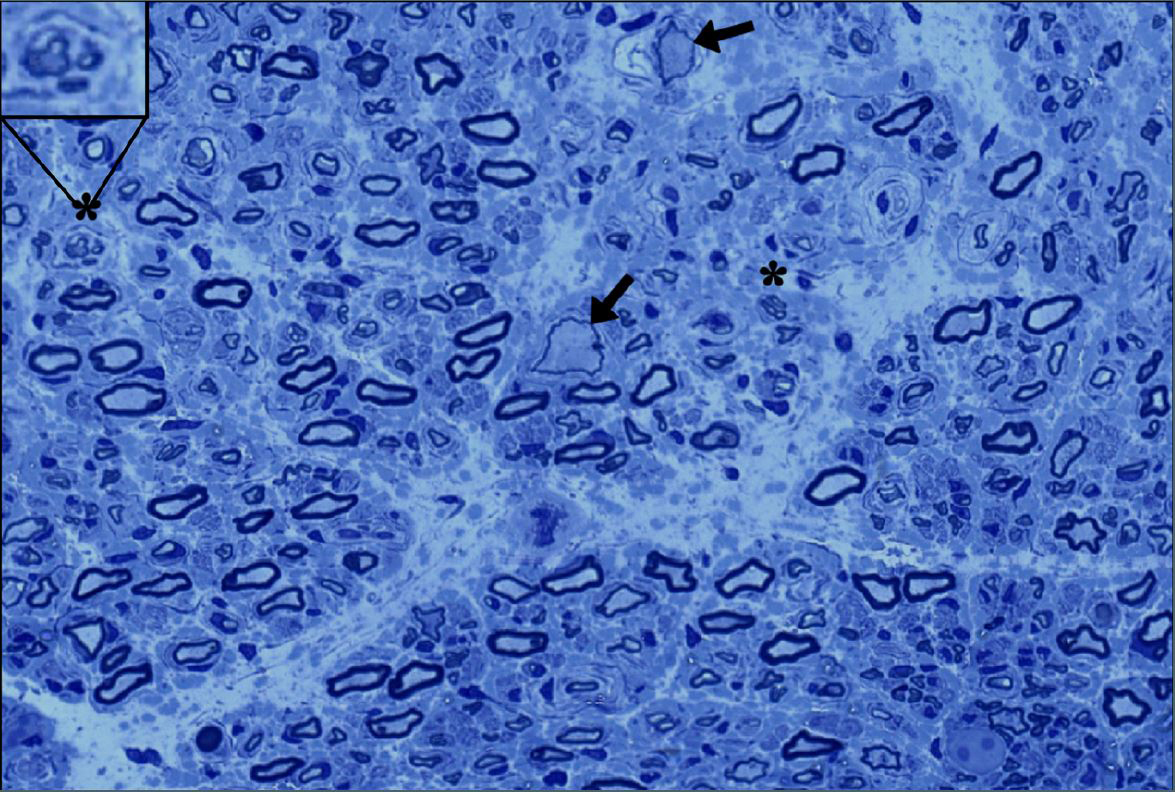

Mutations to the GAN gene result in an inability to break down intermediate filaments, which are cellular structures that make up the framework of nerve cell extensions called axons. Axons are essential for transmission of signals between brain cells. The disease name refers to the enlarged and bloated appearance of the axon under the microscope. As GAN progresses, the axons of motor and sensory nerves break down, resulting in difficulty with movement and sensation because nerve cells cannot communicate with each other.